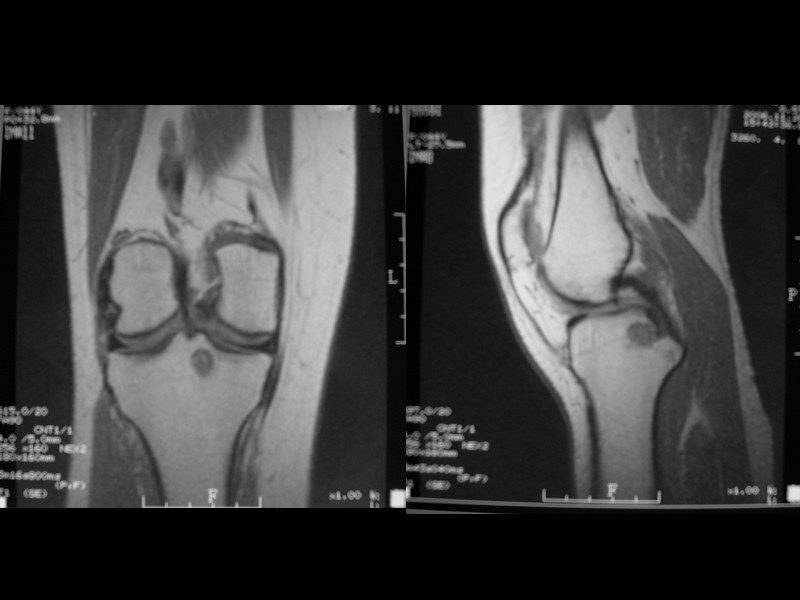

Гигантоклеточная опухоль (Остеокластома) 15% от всех доброкачественных костных опухолей Выявляется в возрасте от 20 до 40 лет Одиночная Преимущественная локализация – метаэпифизы длинных трубчатых костей, реже – кости таза, ниж. челюсть, позвонки Ячеистый тип опухоли – булавовидное вздутие с ячеистой структурой (соты), истончение кортикального слоя, четкая граница от окружающей кости Литический тип – вздутие, полное отсутствие трабекулярного рисунка, дефект кортикального слоя (похоже на метастаз, литическую остеосаркому) Часто осложняется патологическими переломами Малигнизируется часто